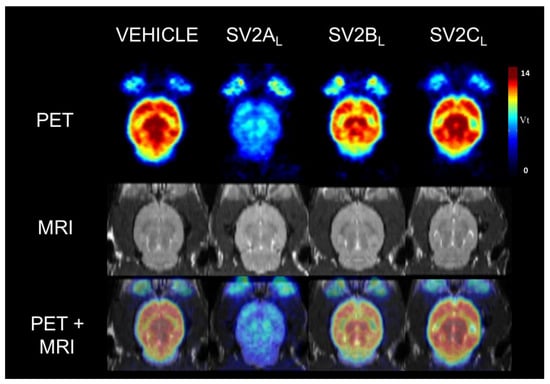

2. Results